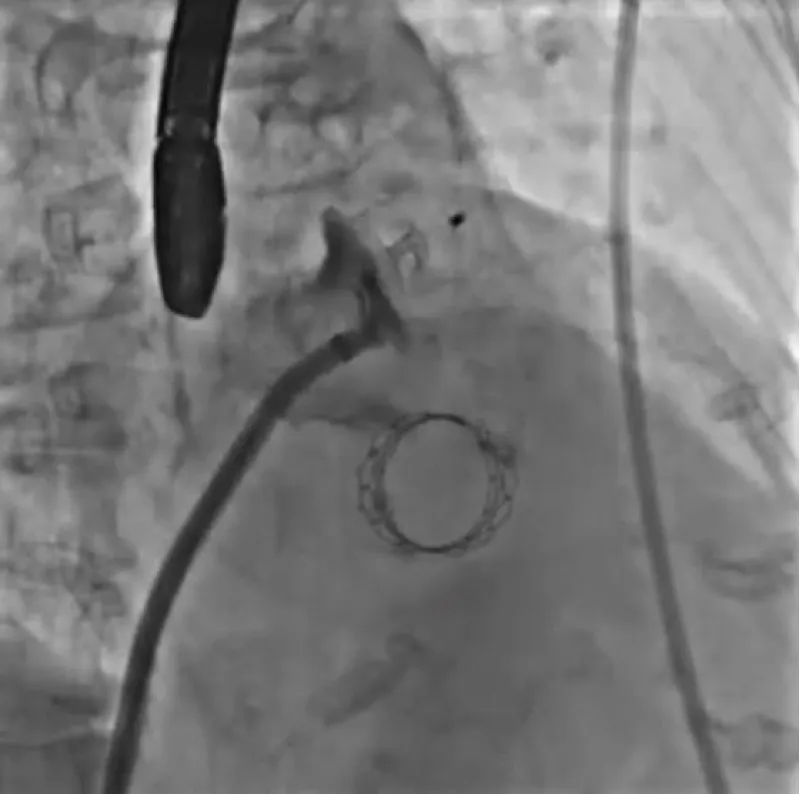

With the support of deep sedation, an angio-guided right femoral access was obtained, and a 12F introducer was advanced. We crossed the aortic valve with an Amplatzer left 1 catheter with a 0.035” wire and exchanged the wire with an extra-stiff Safari. We performed aortic Valvuloplasty with a Nucleus balloon 18 x 40 mm. (Figure 7) Then, we exchanged the wire and advanced an IMPELLA CP device, starting a protected PCI on LM. (Figure 8) An EBU 4.0 catheter was advanced, the stenosis was crossed on the Left Main (LM) and mid-Left Anterior Descending artery (LAD) using a BMW guide wire, and with the aid of a microcatheter a 0.014” Rotawire was positioned, followed by rotational atherectomy using a 1.5 mm burr on LM and mid LAD, (Figure 9) and a 2.0 mm burr on LM alone (Figure 10). This was followed by predilation with a 2.5 x 20 mm SC balloon and the implantation of a 2.5 x 32 mm Synergy drug-eluting stent (Figure 11). Then, the Left Main was predilated with a 3.5 x 12 mm NC balloon, and a 4.0 x 15 mm Xience Sierra drug-eluting stent was implanted and post-dilated with a 4.5 x 8 mm SC balloon (Figure 12). Immediate angiographic control confirmed a successful result. Then we removed the IMPELLA CP device and advanced a 14F e-sheath Edwards on the right femoral artery, crossed the aortic valve with a Safari extra-stiff wire, and performed a Sapien 3 23 mm valve implantation with a good angiographic result (Figure 13). Post-procedural echocardiographic and angiographic assessment confirmed the valve was correctly positioned, with no significant gradient and a minimal residual leak. The procedure was uneventful, and the patient was discharged on the fourth day with triple therapy: Aspirin 100 mg once daily, Clopidogrel 75 mg once daily, and Apixaban 2.5 mg twice daily. At the quarterly follow-up, the patient reported hospitalization for anemia, requiring a transfusion of 3 units of packed red blood cells. Endoscopic exams were negative, and hypochromic, normocytic anemia persisted. Given the patient’s CHA2D2-VASc score of 5, HAS-BLED score of 4, and recent dual Drug-Eluting Stent (DES) implantation, she was admitted for left atrial appendage percutaneous closure. Before this procedure, a repeat coronary angiography showed good results in the previously implanted stents (Figure 14). Subsequently, through a right femoral percutaneous approach using a 12F introducer, a 22 mm Amulet device was positioned for left atrial appendage closure (Figure 15). The procedure was completed without complications. At the 4-year follow-up, the patient presented in good hemodynamic status, with an echocardiographic ejection fraction of 55%. She continued on clopidogrel 75 mg once daily therapy.

Figure 13: Sapien 3 23 mm.